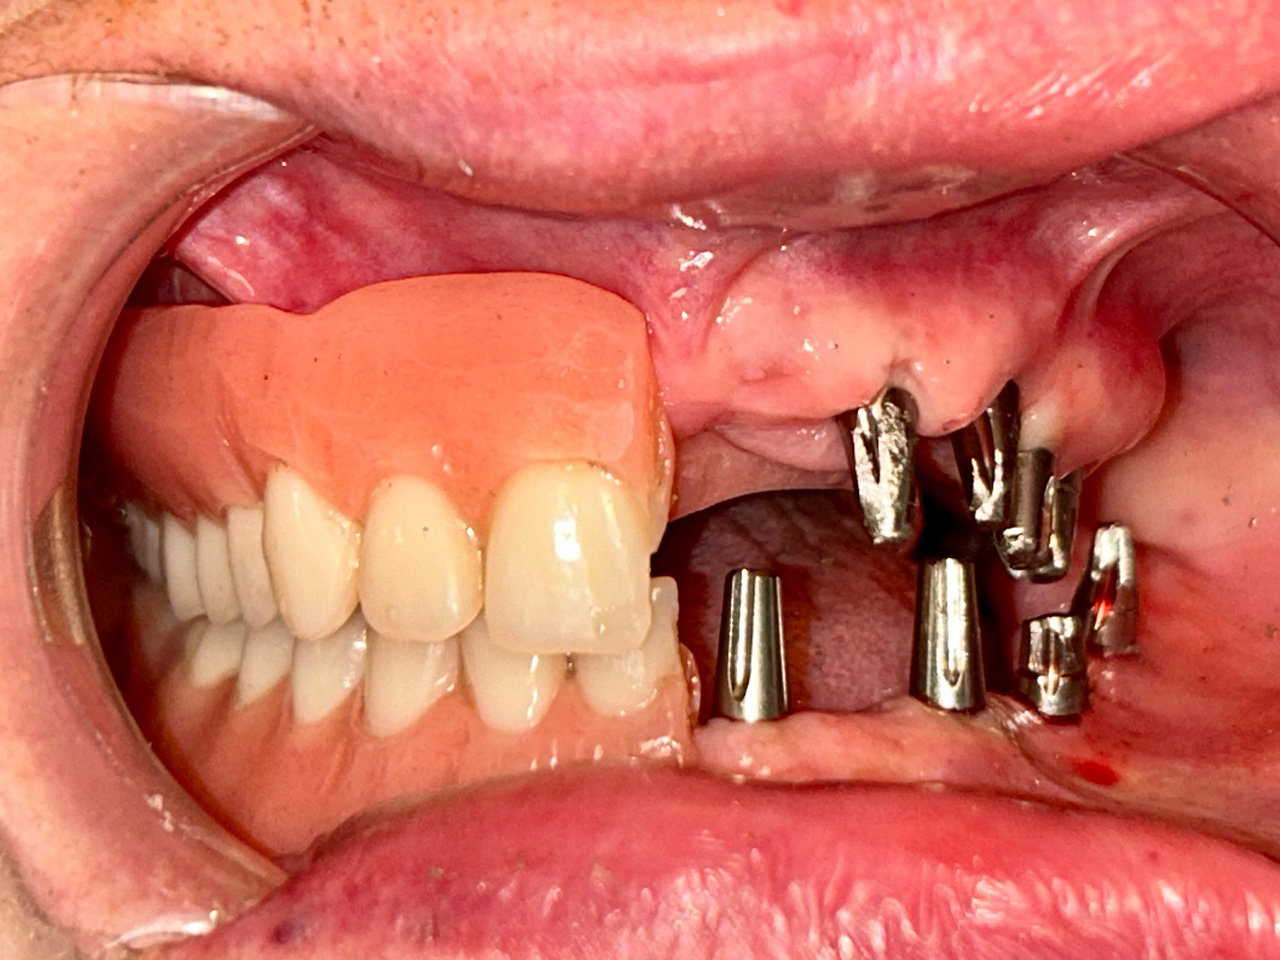

Alsó állcsont teljes rehabilitációja 72 óra alatt

Alsó állcsont teljes rehabilitációja 72 óra alatt, azonnal terhelhető implantátumokkal súlyos paradontitisben szenvedő dohányzó páciens esetében. Az alsó állcsont fogai mind mozogtak az előrehaladott fogágypusztulás miatt.

A fogakat eltávolítottuk, a gyulladt, fertőzött csontot kitakarítottuk, kifertőtlenítettük, majd azonnal implantáltunk.

Svájci, IHDE márkájú, azonnal terhelhető implantátumokat helyzetünk be, és ezekre harmadnapra rögzített, hosszútávú, fémvázas, esztétikus műanyaggal leplezett hidat ragasztottunk be.

Ezt az ideiglenes hidat a sebek gyógyulása miatt használjuk, de tartóssága miatt véglegesként is használható. A legtöbb esetben, ahogy itt is, 6 hónap múlva porcelán hídra cseréljük, a teljes gyógyulás után.